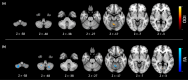

Results: Eighteen MYC/DYT-SGCE patients and 24 HVs were analyzed. MYC/DYT-SGCE patients showed an increase of ODI and a decrease of FA within their motor cerebellum. More severe dystonia was associated with lower ODI and NDI and higher FA within motor cerebellar cortex, as well as with lower NDI and higher ISOVF and MD within the corticopontocerebellar and spinocerebellar pathways. No association was found between myoclonus severity and diffusion parameters.